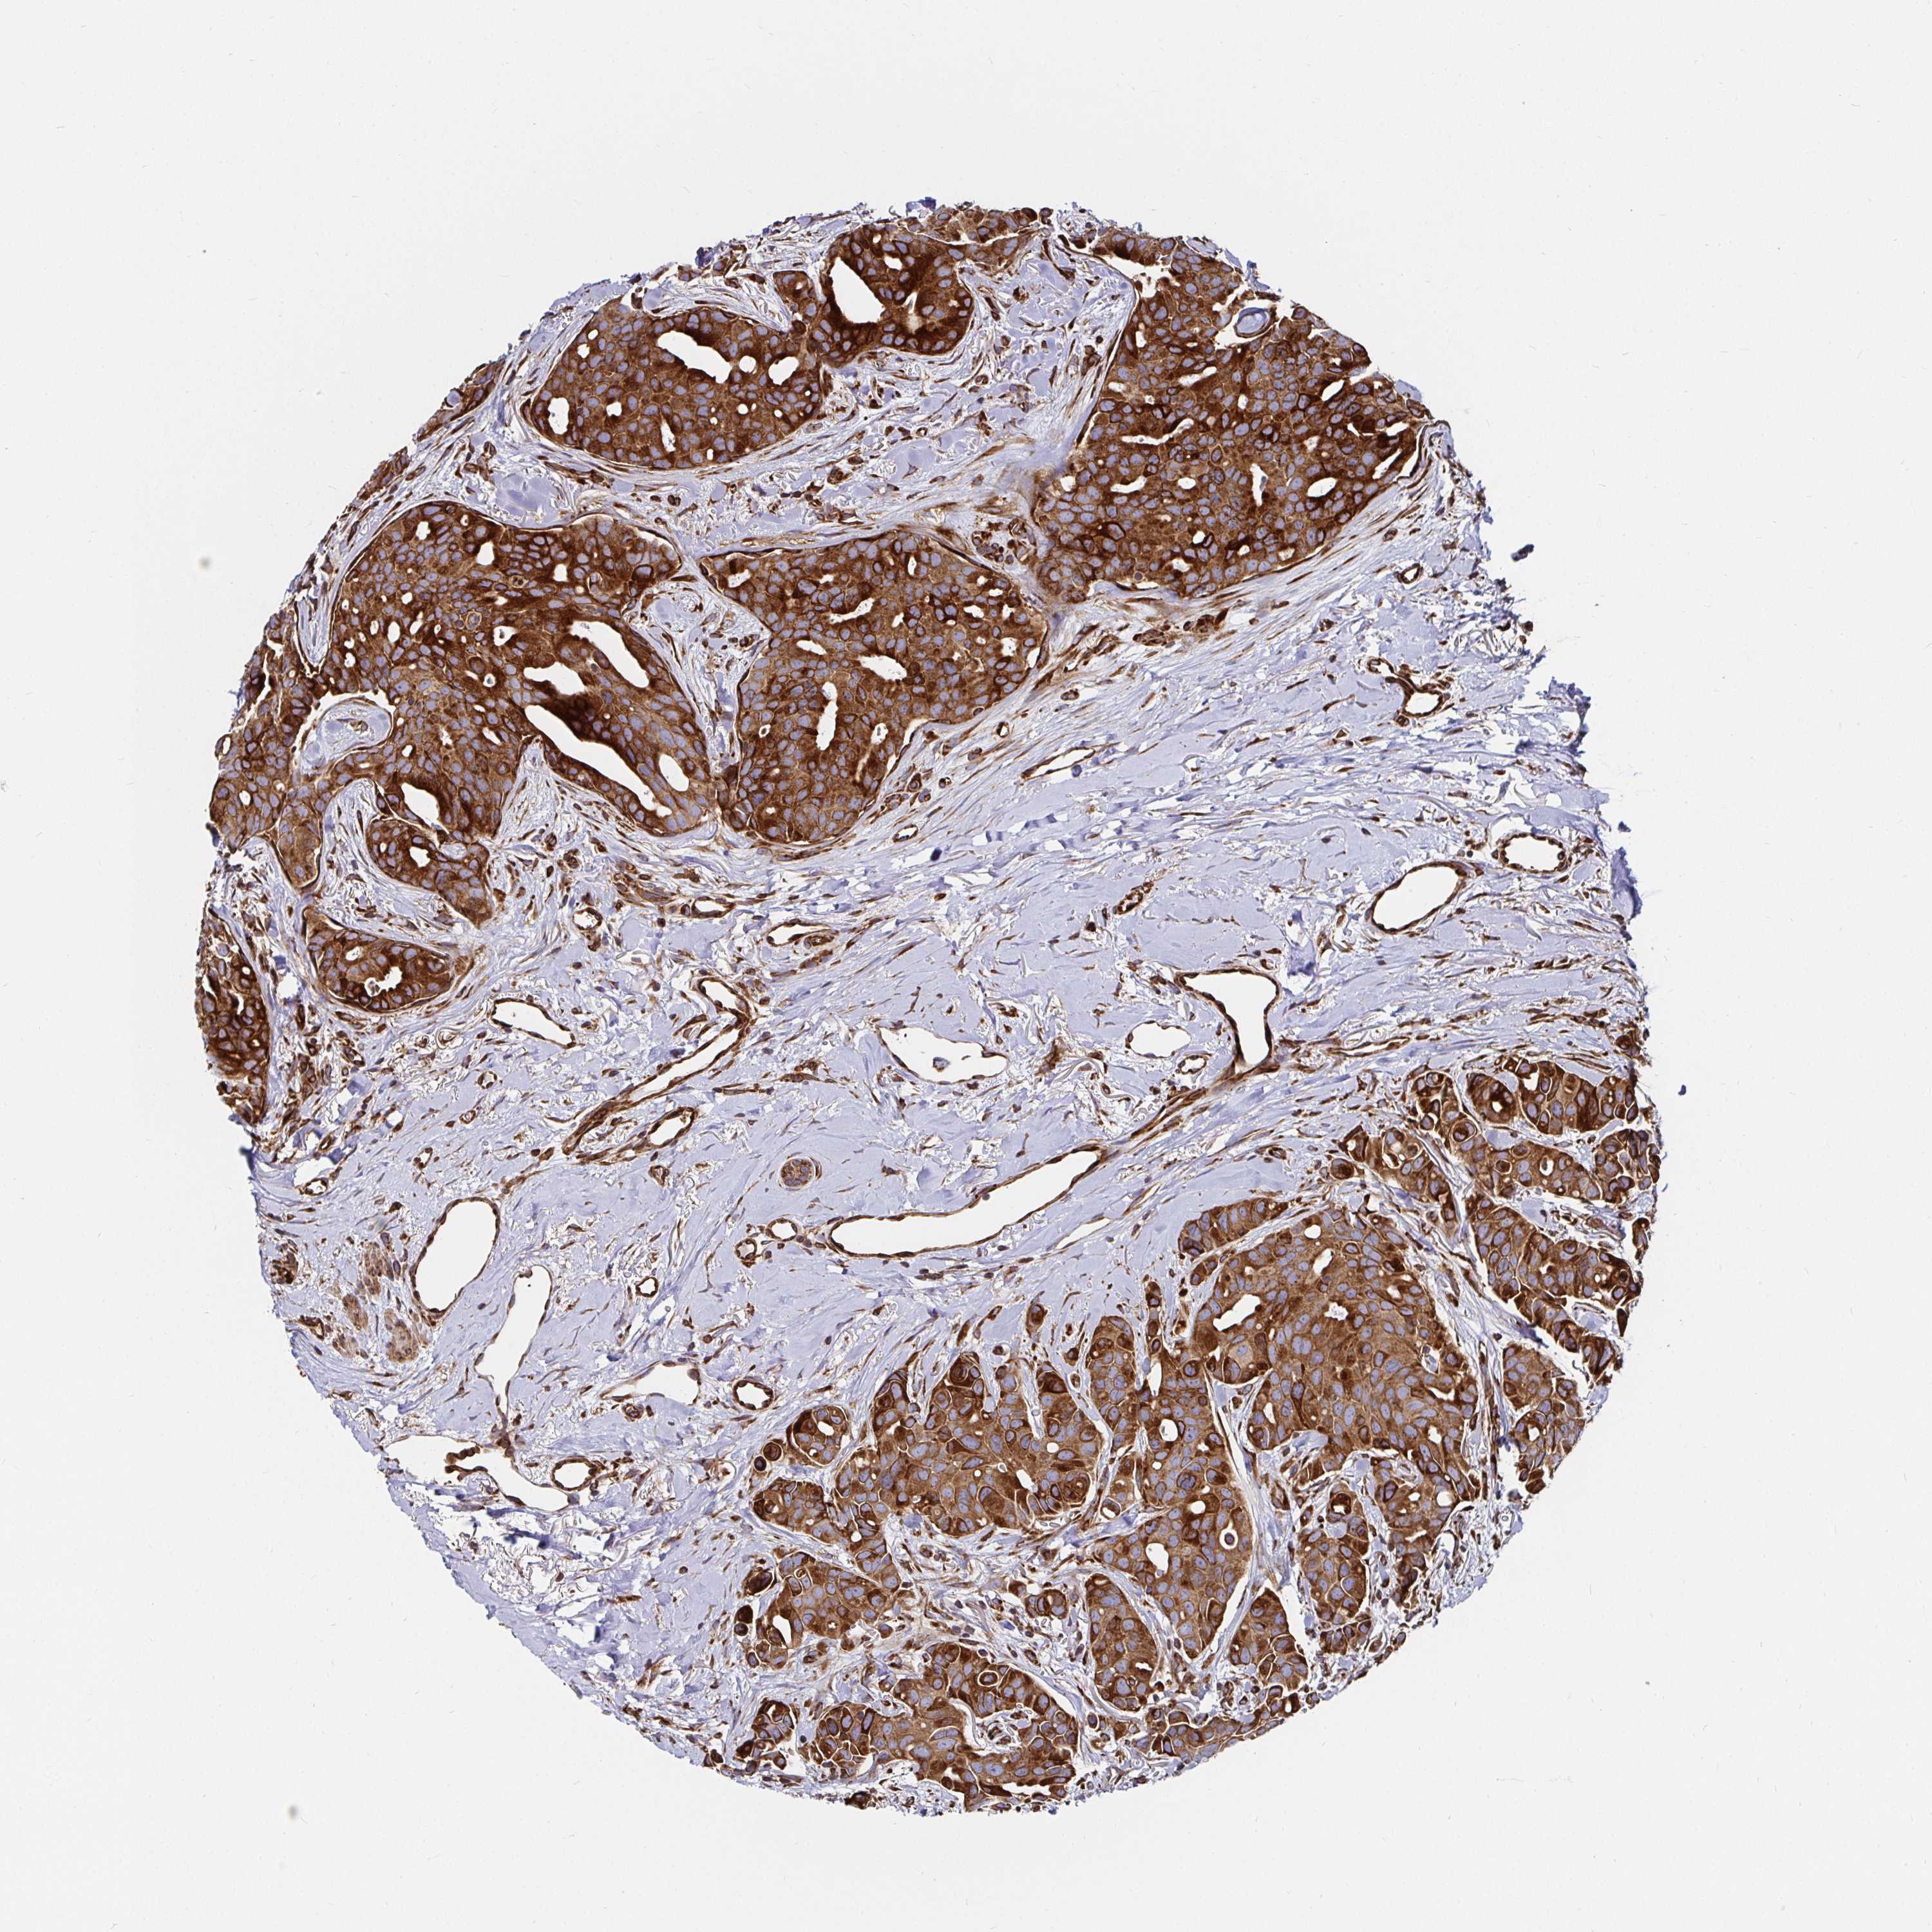

BRCA TCGA BRCA VALIDATION PROTEIN EXPRESSION

ANTIBODIES

AND

VALIDATION